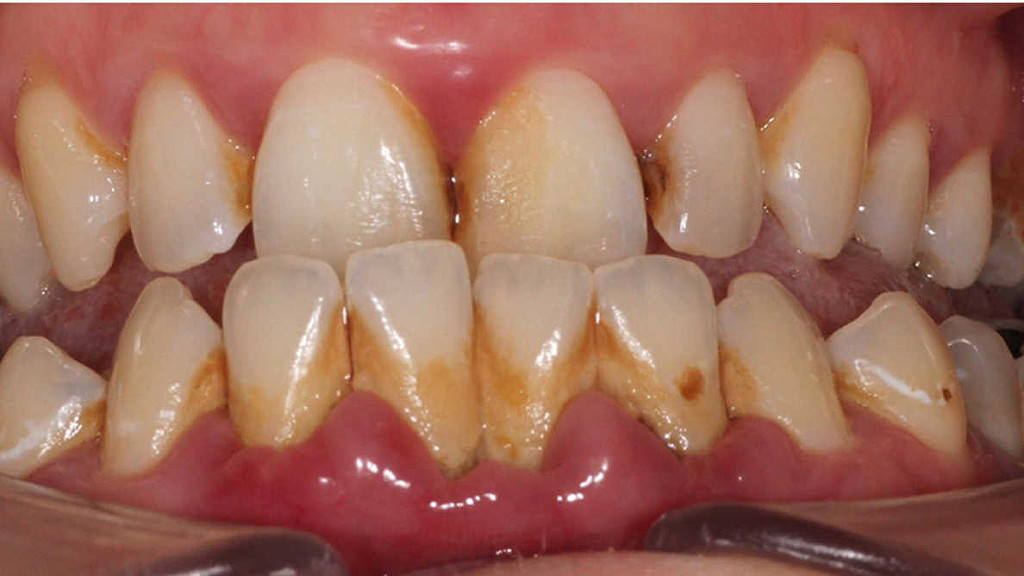

Oral biofilms, a concern for all dental professionals

Biofilms are a collective of one or more types of microorganisms that can grow on many different surfaces. Microorganisms that form biofilms include bacteria, fungi and protists.

One common example of a biofilm dental plaque, a slimy buildup of bacteria that forms on the surfaces of teeth. Pond scum is another example. Biofilms have been found growing on minerals and metals. They have been found underwater, underground and above the ground. They can grow on plant tissues and animal tissues, and on implanted medical devices such as catheters and pacemakers.

Oral biofilm is medically important because it has broad implications for maintaining not only oral health but also systemic health. It is estimated that biofilms account for over 80% of microbial infections in the body. Research has undoubtedly shown that biofilm-dependent infections, including oral diseases such as caries, and periodontal and endodontic disease, thus pose major public health and cost concerns globally.

Periodontal disease, in particular, is considered one of the most prevalent diseases worldwide, affecting up to 50% of the world’s adult population, according to FDI World Dental Federation. Previous research has established connections between periodontal disease and preterm births, low birthweight, diabetes, and risk factors associated with cardiovascular disease and stroke. Globally, periodontitis is responsible for an estimated US$54 billion per year in lost productivity and a major portion of the US$442 billion spent annually on oral disease, according to the European Federation of Periodontology.

Education on oral biofilm:

Until the early 1990s, dentists confined their treatment for combating oral plaque to removing calculus twice a year because there was only limited understanding of biofilm. Over the past decades, research on and improved knowledge about the parameters that determine the development of oral disease have spurred the development of new preventive strategies. For instance, piezoceramic instruments and low-abrasion powders have made professional biofilm management safer, minimally invasive and more comfortable for both the patient and the dental practitioner. Moreover, the launch and further development of AIRFLOW devices by EMS fundamentally changed biofilm management and eventually resulted in the development of Guided Biofilm Therapy, an innovative concept for contemporary prophylaxis.

“As biofilms can be found on all oral surfaces, it is clear that all dental disciplines, ranging from dental hygienists to orthodontists, are highly affected by oral biofilm and its sequelae,” highlighted Beikler. “Unfortunately, prevention is sometimes still considered to be toothbrushing augmented by some kind of professional tooth cleaning. However, the whole oral cavity should be the therapeutic focus of a systematic preventive approach.”